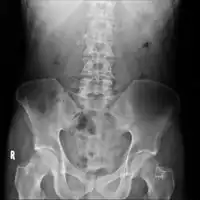

On CT scan, pancreatic and bile duct dilatation, atropy of pancreas, multiple calcifications of the pancreas, and enlargement of pancreatic glands can be found.[12]

Chronic pancreatitis

Chronic calcific pancreatitis

Acute on chronic pancreatitis